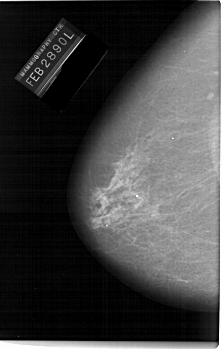

A_1144_1.LEFT_MLO

LEFT_MLO LINES 6721 PIXELS_PER_LINE 3886 BITS_PER_PIXEL 12 RESOLUTION 43.5 NON_OVERLAY